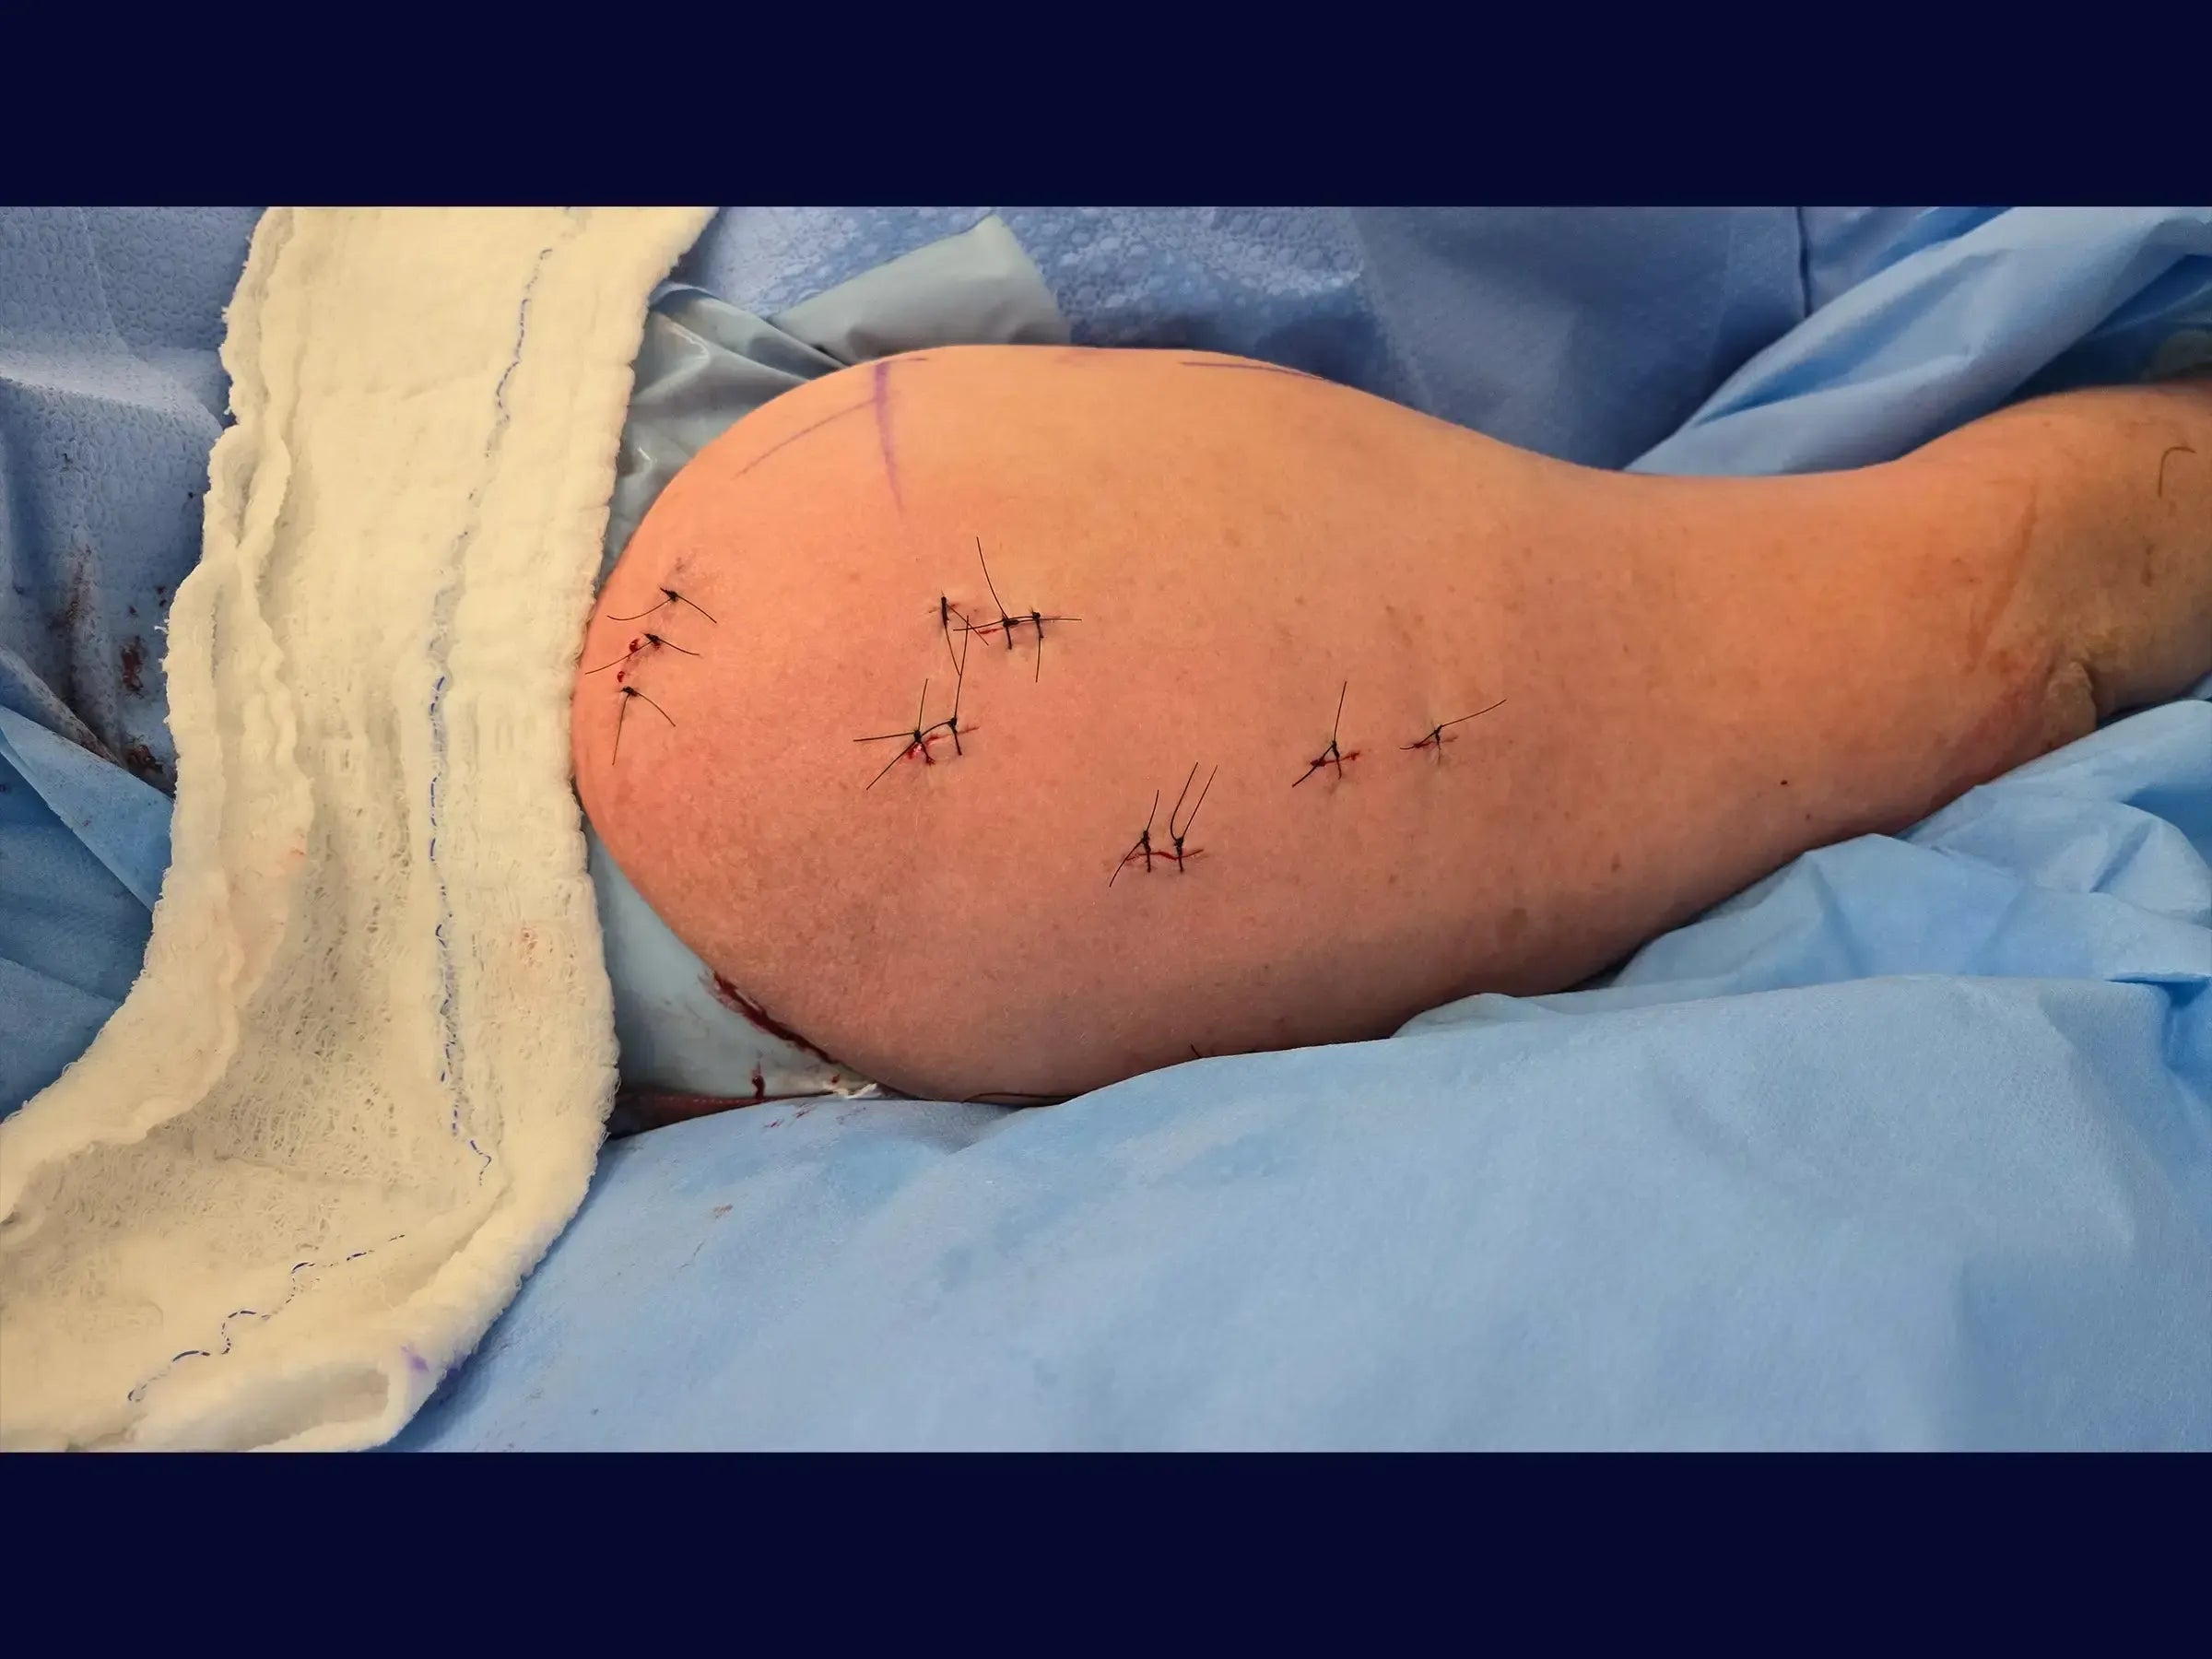

- Minimally invasive approach.

- Systematized Percutaneous Blocking: Protocols for safe and effective insertion of proximal and distal locking screws.